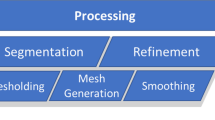

The production process begins with imaging of the original structure, e.g. computed tomography from patients (clinical setting), cadaveric specimens, anatomical models or phantoms (experimental setting). The resulting data sets are stored in Digital Imaging and Communications in Medicine (DICOM) file format. A virtual three-dimensional model is generated from the DICOM data sets by segmentation. In most cases the standard tessellation language (STL) file format is used for saving a model. This format is a translation of the model into a three-dimensional mesh structure of triangles and normal vectors. These STLs are prone to errors such as artefacts, mesh gaps and misorientation of the normal vectors, but can be corrected by various, partly automated, partly manual repair methods including smoothing (digital editing). However, if the resolution of the mesh is low, the model may deviate significantly from the original (Fig. 1).

Digital editing techniques help to generate a print-STL file of good quality, which is translated into a machine-readable code (slicing). This code, which may be printer-specific, is then interpreted by the 3D-printer in order to build a 3D object layer by layer. After the built is completed, a material and printing technology-dependent post-processing is necessary, e.g. removal of support structures or a curing with ultraviolet light.

Figure 2 shows the process for the production of patient-specific 3D-printed anatomical models.